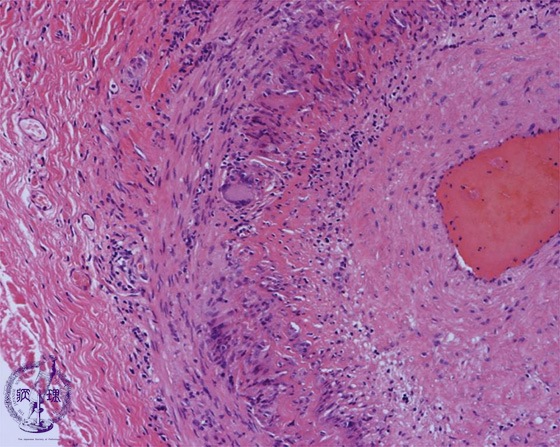

- (14)Giant cell arteritis

Microscopic image (HE, intermediate power view): Infiltration of foreign body type multinucleated giant cells with destruction of the medial elastic laminae is observed.